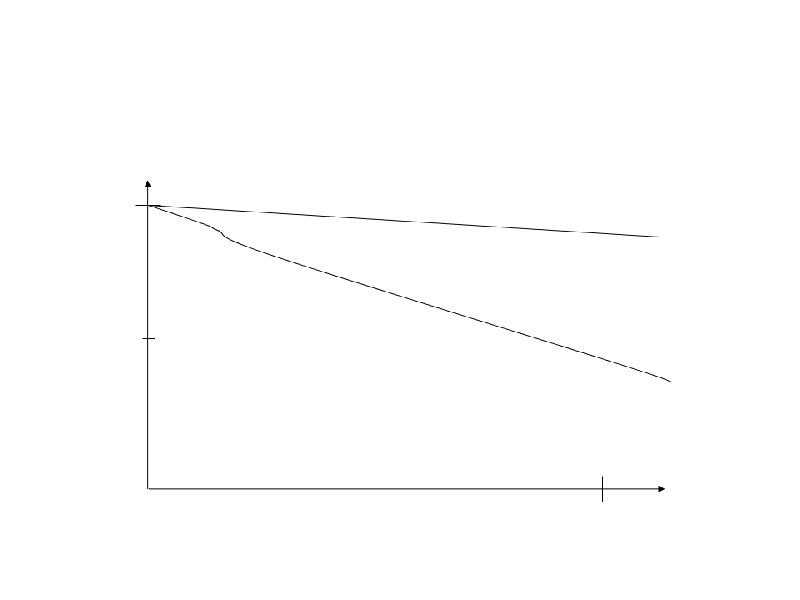

Время удвоения лимфоцитов менее 6 месяцев Время удвоения лимфоцитов более 6 месяцев Стадия на момент диагноза III – IV / C (Rai / Binnet) Возраст менее 65 лет I – II / A Возраст более 65 лет ZAP-70 < 20% Соматическая мутация (-) Соматическая мутация (+) 17 p делеция (p 53 мутация), 13 q делеция 11 q делеция, 12 q трисомия CD 38 (+) CD 38 (-)